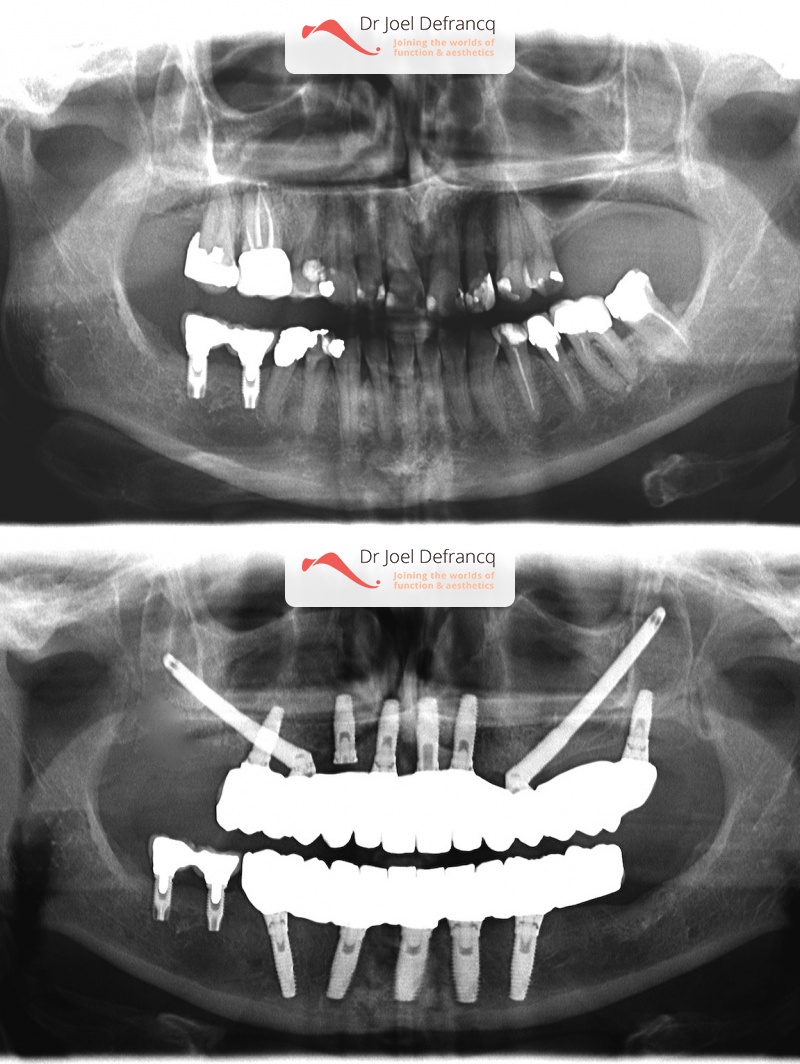

Debbora: Implant concept "all-on 4" & lipofilling discrete lip lipofilling

Dentale diagnose

- Klasse II divisie 2

Behandeling tandheelkundige implantaten

- Vaste tanden op implantaten (bovenkaak)

- Vaste tanden op implantaten (onderkaak)

- Zygoma implantaten